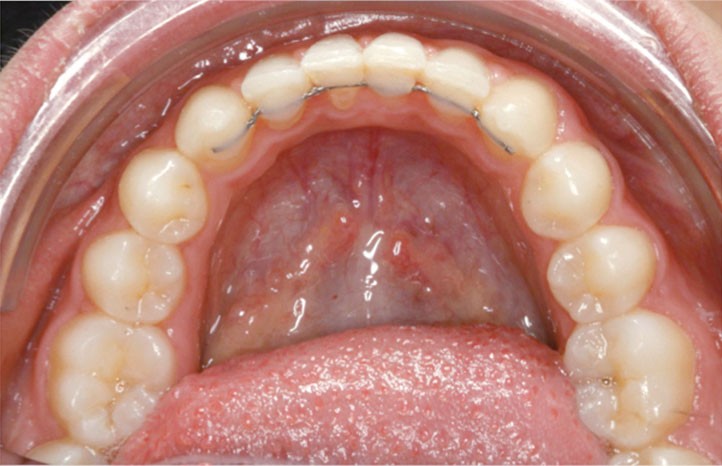

Les vues endo-buccales après extraction de 52 montrent des relations occlusales de classe II, un léger encombrement incisif mandibulaire et une tendance à la fermeture spontanée des espaces des incisives latérales confirmant le choix thérapeutique d’une fermeture d’espace (fig. 2).